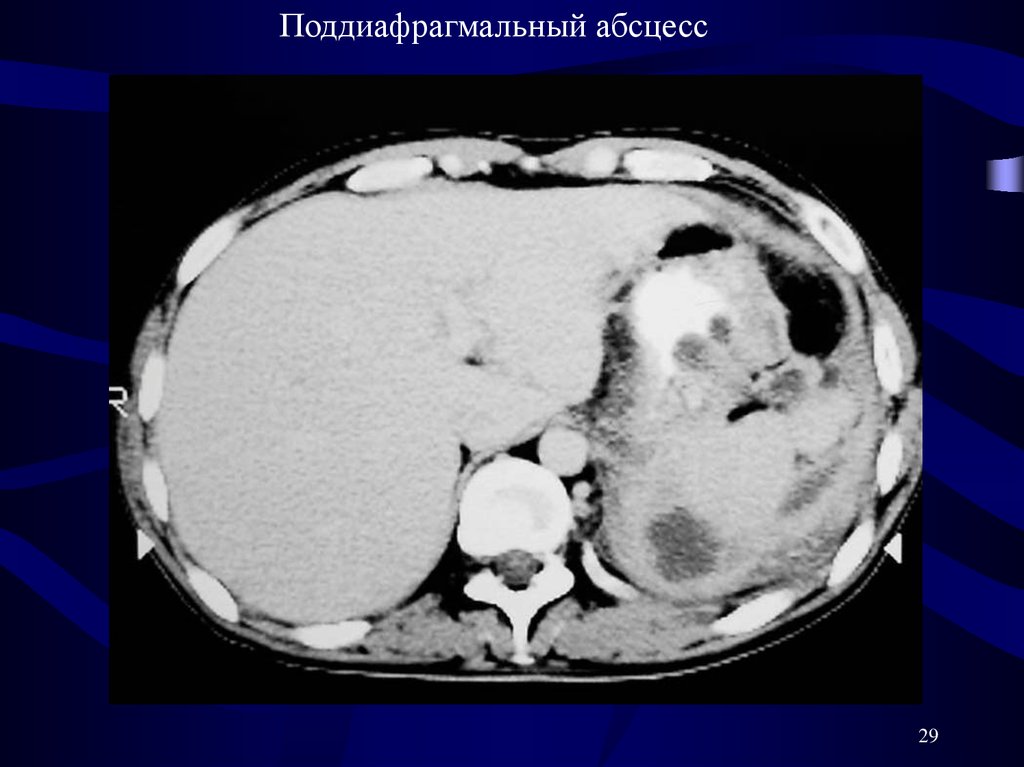

Поддиафрагмальный абсцесс